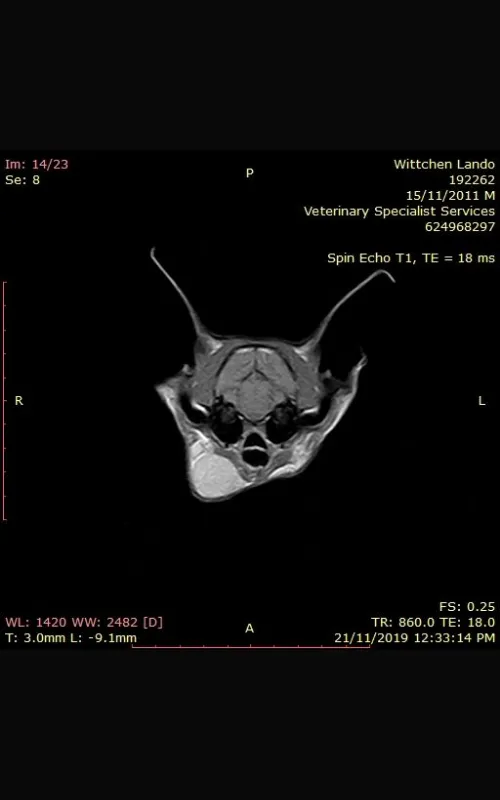

Under the care of Dr Wan Ju Jao, Lando had surgery to remove the affected lymph node and reduce the fungal burden. Testing of the tissue confirmed severe lymphadenitis caused by cryptococcosis, and a serum cryptococcal antigen test showed high levels. Analysis of his cerebrospinal fluid also confirmed the infection had reached his central nervous system.

Ultrasound result